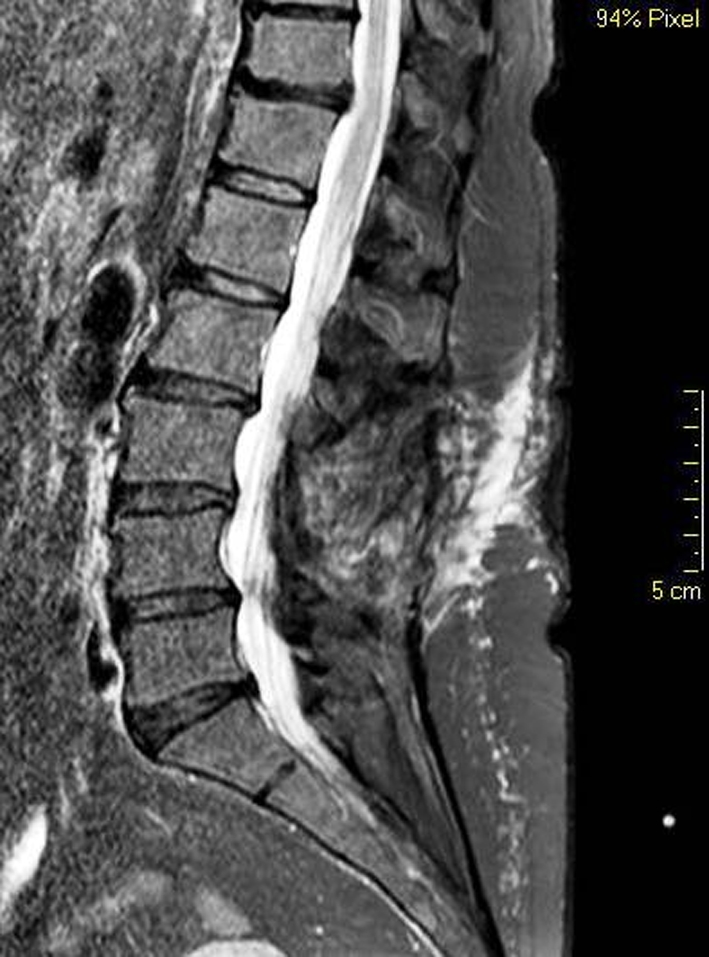

A lumbo-sacral MRI showed a well encapsulated paramedian multilobar mass under the L3 body, along the left L3 root (Figs. 3, 4).

Fig. 4.

Case 2, sagittal preoperative T2 MRI sequence